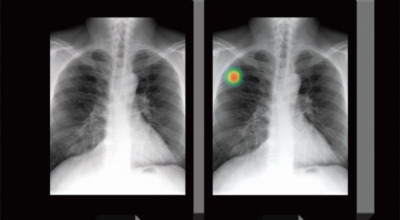

폐암 초기증상

폐암 초기증상 ① 체중감소

폐암 초기 증상으로는 다른 암과 마찬가지로 입맛 감소와 전신 쇠약감이 나타날 수 있습니다. 체중이 갑자기 줄어들기도 하는데요, 최근 식사량을 줄이거나 식단 관리를 하지 않았음에도 평소 체중의 5% 이상이 감소했다면 검진을 받아보는 것이 좋습니다.

암세포는 정상세포보다 빠른 성장 속도로 많은 에너지를 필요로 하기 때문에, 암의 진행에 따라 체중 감소가 나타날 수 있습니다. 특별한 원인 없이 6개월 내에 10kg 이상, 또는 체중의 10% 이상이 줄어들었다면 폐암 초기 증상일 가능성이 있습니다.

폐암 초기증상 ② 기침

기침은 폐암 초기 증상 중 가장 흔하게 나타나는 증상입니다. 폐암 환자의 약 75%가 잦은 기침을 겪는데, 감기와 구분이 어려워 대수롭지 않게 넘기는 경우가 많으니 주의가 필요합니다. 따라서 기침이 오랜 시간 지속된다면 꼭 진찰을 받아보시길 권합니다.

폐암 초기증상 ③ 쉰 목소리

성대를 조절하는 신경이 폐와 기관 사이 공간을 지나가는데, 암이 진행되면서 이 신경을 침범하면 성대 마비 증상이나 목소리가 쉬는 현상이 나타날 수 있습니다.

폐암 초기증상 ④ 가슴 통증

폐암 초기 증상 중 하나로 가슴 통증이 있습니다. 폐암 환자의 약 3분의 1 정도가 흉통을 호소하는데요, 이는 폐 가장자리 부분에 종양이 생기고, 그 종양이 암세포를 생성하며 흉벽과 흉막에 닿아 통증을 유발하기 때문입니다.

흉통은 여러 원인으로 발생할 수 있지만, 폐암에서 기인한 흉통은 지속적으로 쿡쿡 찌르는 듯한 느낌과 함께 가벼운 통증이 아닌 둔탁한 통증이 동반되는 경우가 많으니 주의가 필요합니다.

폐암 초기증상 ⑤ 호흡곤란

폐암 초기 증상 중 하나로 호흡곤란이 나타날 수 있습니다. 폐암 환자의 약 50%가 숨이 차다고 느낀다고 알려져 있어요. 이는 암 덩어리가 커져 숨이 가빠지는 경우도 있지만, 폐암으로 인한 폐 허탈, 상기도 폐색, 흉막 삼출 등이 호흡곤란을 일으키기도 합니다. 평소와 달리 숨이 차고, 숨을 들이쉬거나 내쉴 때 쌕쌕거리는 소리가 난다면 폐암 초기 증상을 의심해 볼 필요가 있습니다.

폐암 초기증상 ⑥ 혈담

폐암 초기 증상으로는 혈담이 있습니다. 혈담은 쉽게 말해 가래에 피가 섞여 나오는 경우를 뜻합니다. 폐암이 폐 중앙부 기관지 근처에 위치할 경우 나타나는 혈담은 폐암 환자의 25% 이상이 경험하는 증상입니다. 만약 기침할 때 심한 가래나 혈담이 섞여 나온다면 즉시 병원을 방문하시길 권합니다.